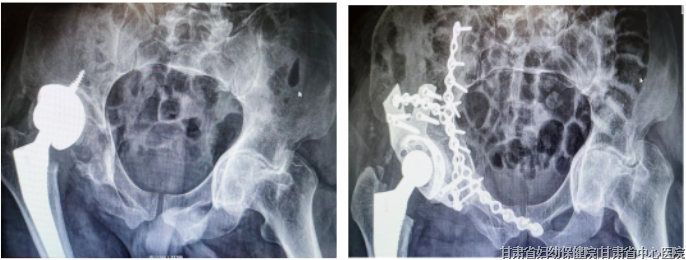

02 骨折脱位痛不欲生,先止痛再治疗

前不久,甘肃省中心医院骨科收治了一名外院行髋关节假体置换后高处坠落再次骨折脱位的患者,该患者辗转兰州市多家省级医院未被接收后就诊于我院急诊科,院前查体时患者疼痛剧烈,阿片类药物几乎无效,立即行床旁超声引导下神经阻滞,患者疼痛控制良好。

骨科与血液肿瘤科协作超声引导完成人工干细胞病灶区植入,与麻醉科协作完成患者围术期镇痛管理